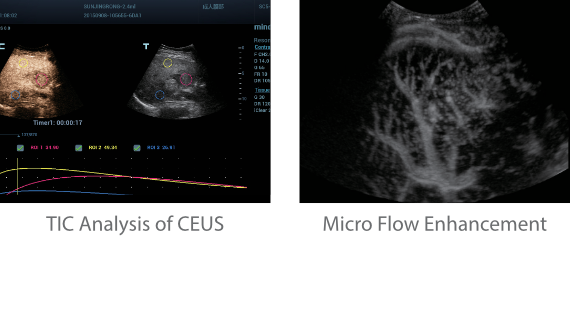

Обеспечивая качество изображения уровня премиум, Resona 7 также повышает клинические возможности исследования при помощи революционной системы V Flow, предназначенной для оценки гемодинамических показателей сосудов; обеспечивает интеллектуальное получение из 3D данных наиболее важных проекций для диагностики ЦНС плода. Сочетая в себе интуитивно понятное сенсорное управление с распознаванием жестов и все важные клинические характеристики, передовая система Resona 7 настоящая новая волна в сфере ультразвуковых инноваций.Благодаря перечисленным выше характеристикам, Resona 7 является доступным решением премиум-класса, которое удовлетворяет высоким требованиям клинической точности и эффективной диагностики в условиях современной перегруженной больничной среды.